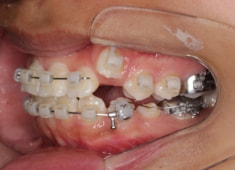

治療開始時

治療開始から5ヶ月後